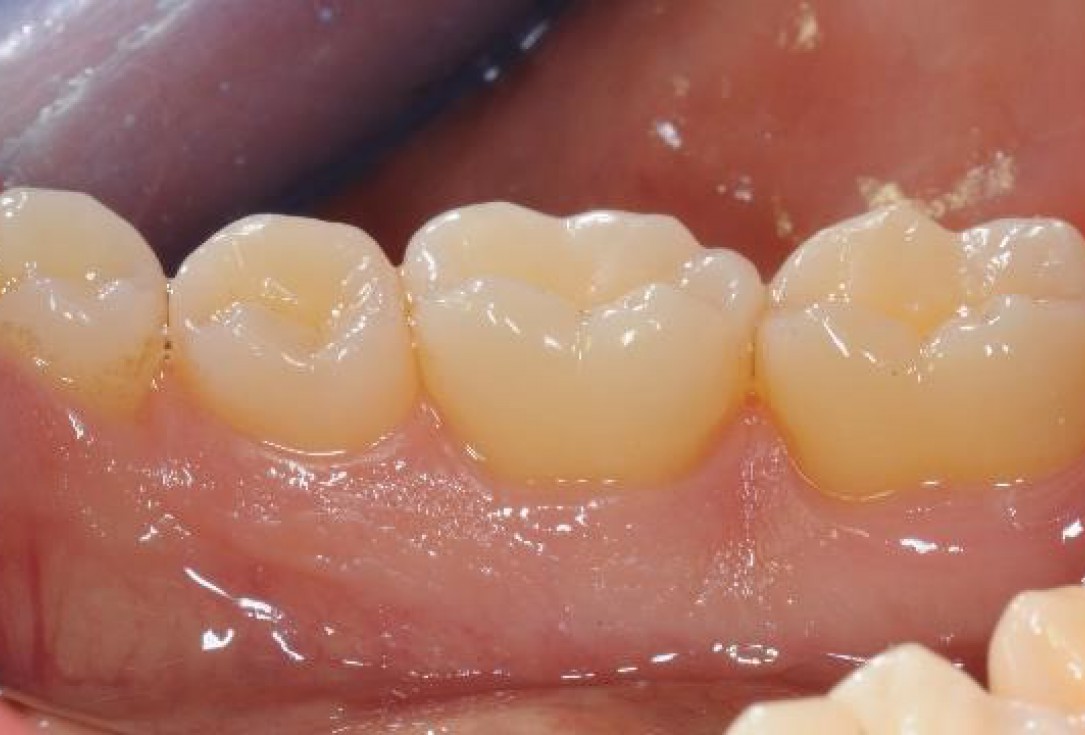

Pre-operative clinical situation. Shallow multiple adjacent gingival recessions in the first quadrant.